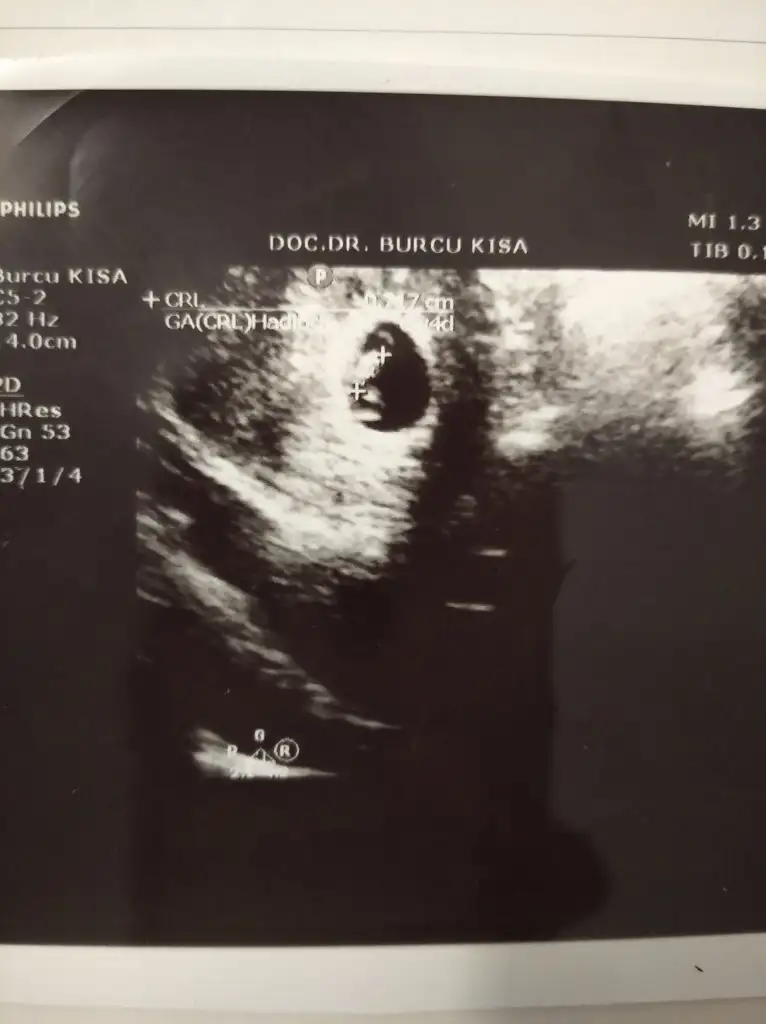

Bi yorum da ben istiyeyim sizden çok belli belirsiz ama belki tahminleriniz olur 🙈 ortada duruyor benim bebiş 😂😂

Canım tam ortada durmuş Ramziye göre bilemedim bir de ManyakPrenses ManyakPrenses baksın... Ama kese şekli fasülye gibiyse erkek diyorlar yanılmıyorsam yuvarlaksa kız.. Fasülye gibi duruyor seninki 😊 ama bu çok tutan bir şey değil :))